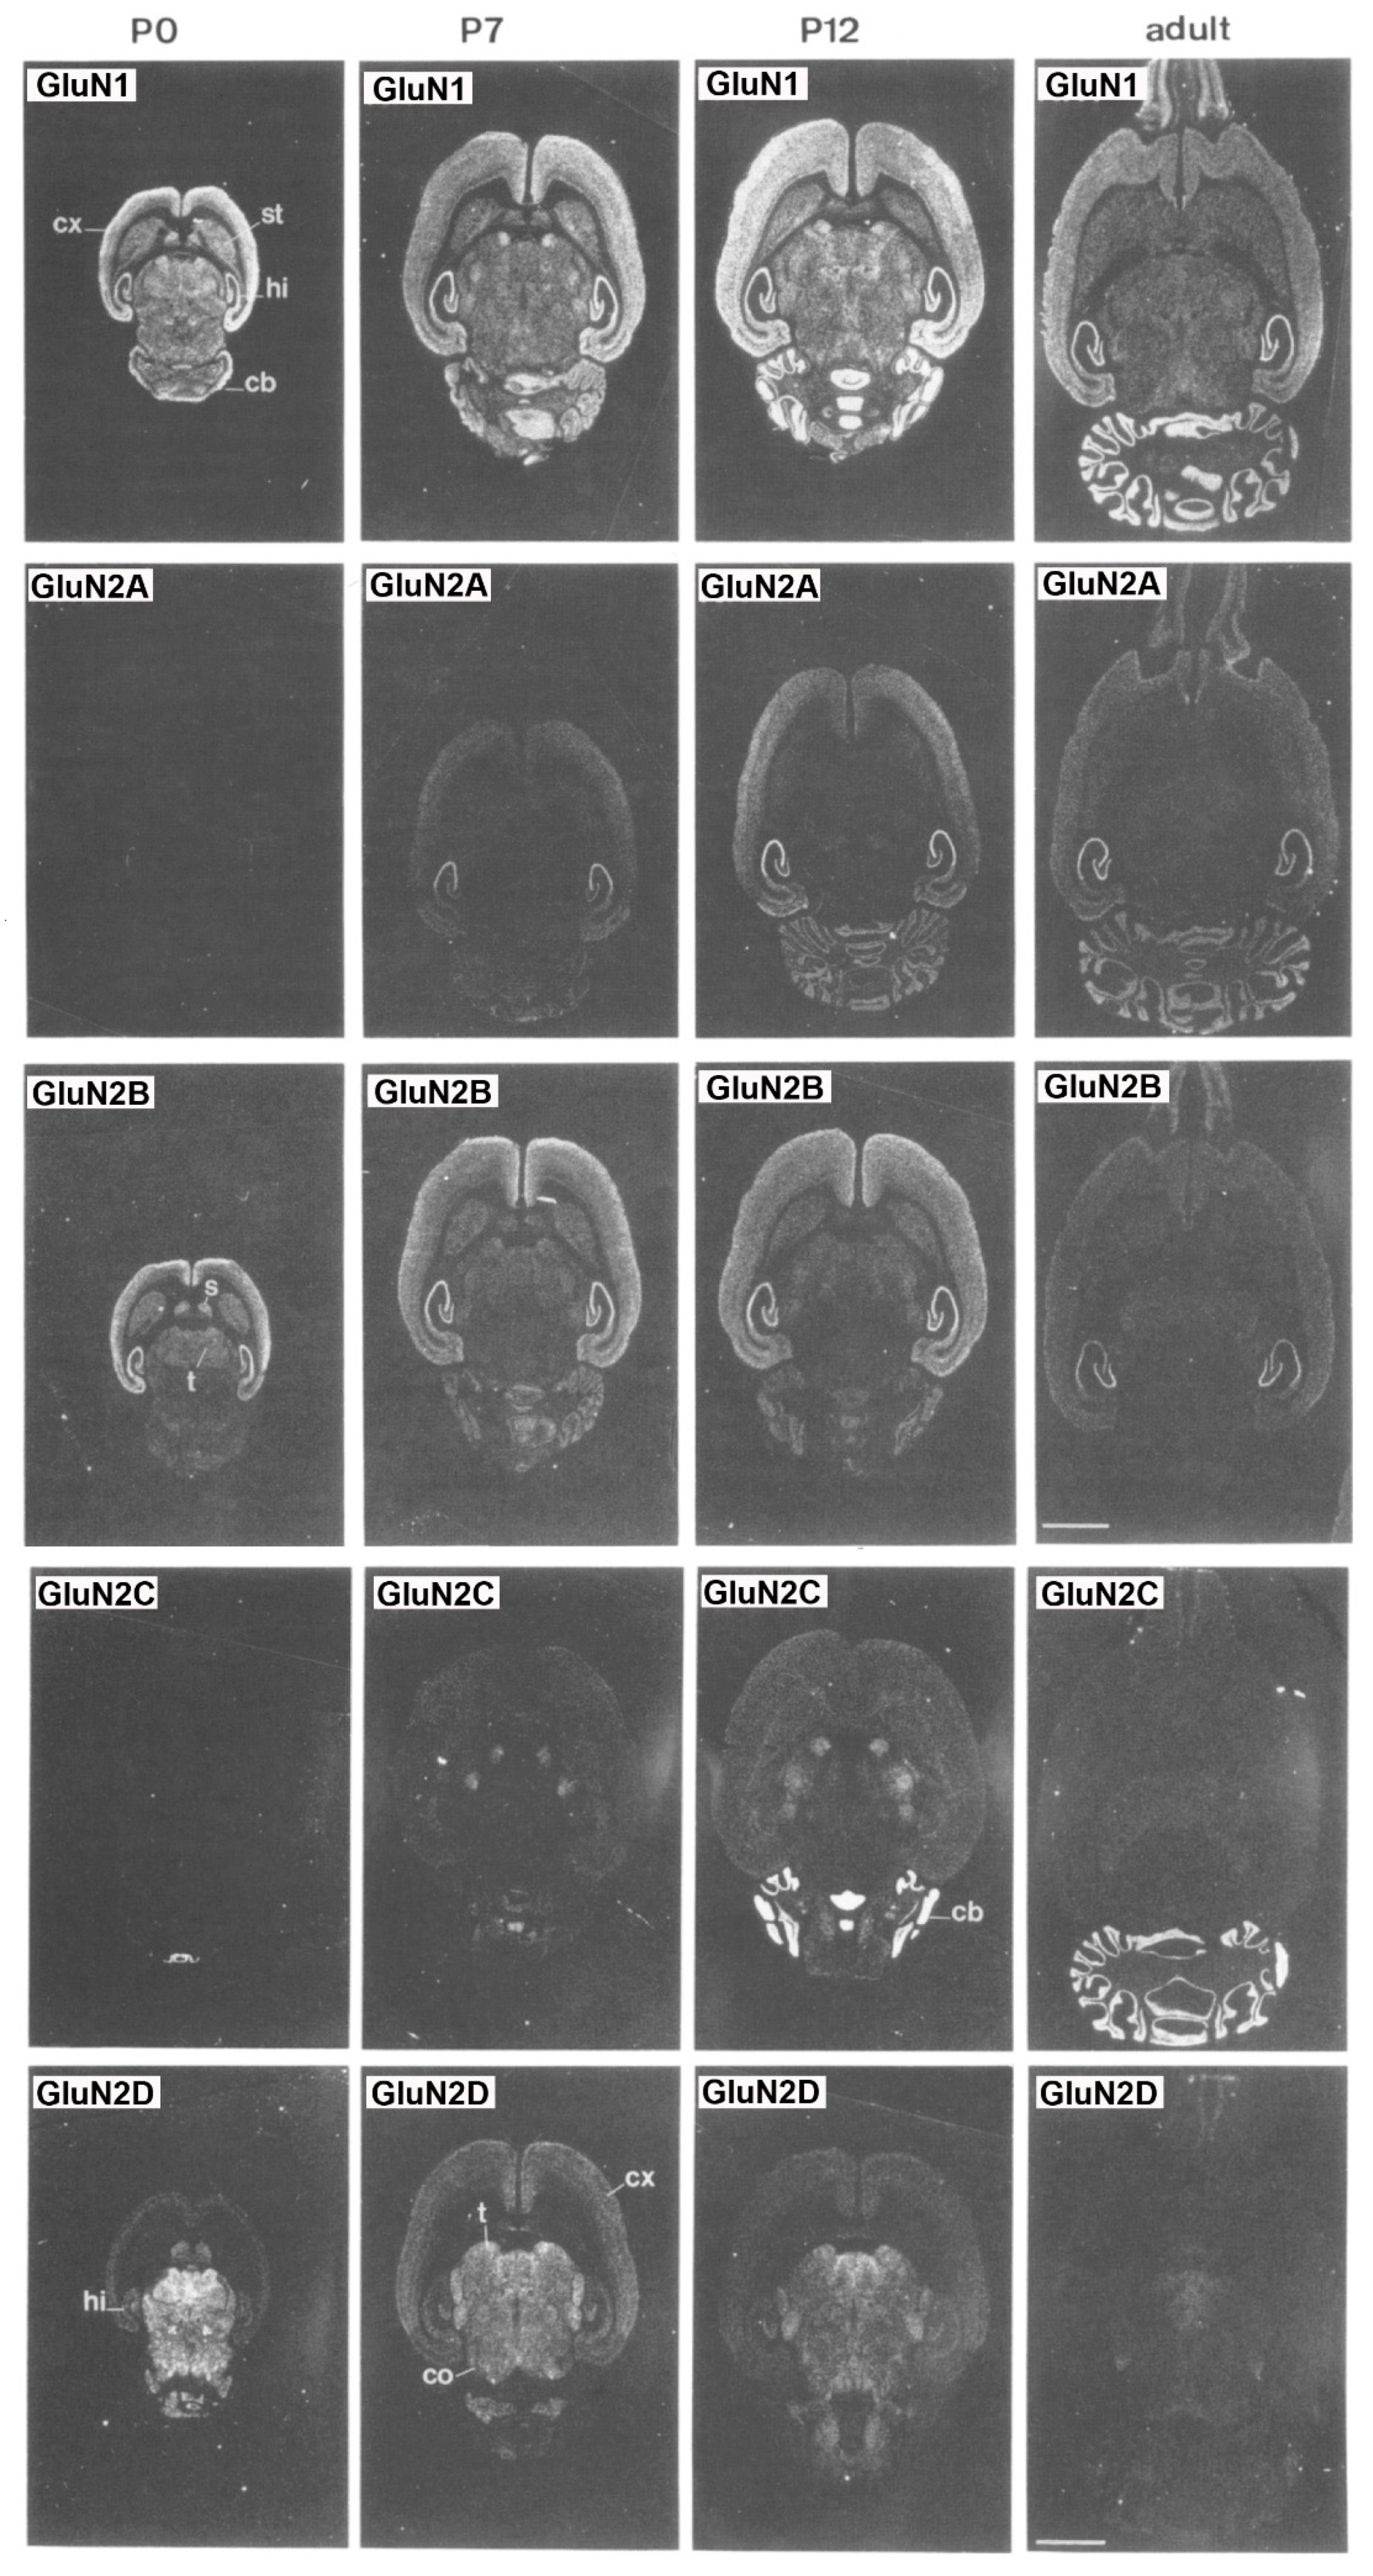

Overall, subunit composition of NMDARs changes along development and varies in different brain regions, which might influence the direction of synaptic plasticity. As depicted in Figure 2, the four glutamate-binding GluN2A-D subunits, in addition to the obligatory GluN1 subunit, are the most prominent subunits in the central nervous system (CNS) [9]. Cortical, hippocampal and striatal neurons in rodents are enriched in GluN2A and GluN2B subunits [8,10,11]. The GluN2D subunit is also present in the hippocampus, but only in younger rats, being undetectable in the adulthood [8]. In contrast, GluN2C subunits are practically restricted to cerebellum with low levels of expression in retrosplenial cortex and thalamus [8,12]. NMDARs are found mainly postsynaptically, although an important subset of them is also found extrasynaptically. The activation of synaptic NMDARs generally promotes synaptic and cell survival, whereas overactivation of extrasynaptic NMDARs by an excess of glutamate can be neurotoxic and induce cell death [13]. It has been reported that GluN2A subunits are predominant at the synapses, whereas GluN2B and GluN2D are localized, though not exclusively, to extrasynaptic compartment [14,15,16,17]. Thus, GluN2A-containing receptors have been reported to contribute to synaptic plasticity, whereas GluN2B-selective antagonists may possess neuroprotective properties.

Figure 2.

Distribution of the GluN1, GluN2A, GluN2B, GluN2C and GluN2D receptor subunit mRNAs. Postnatal developmental profiles of transcripts in horizontal rat brain sections from P0, P7, P12, and adult rats. Abbreviations: cb, cerebellum; cx, cortex; hi, hippocampus; s, septum; st, striatum; t, thalamus. Bar, 3.4 mm. “Reprinted from Neuron, Vol 12, number 3, H. Monyer, N Burnashev, D.J. Laurie, B. Sakmann, P.H. Seeburg, Developmental and regional expression in the rat brain and functional properties of four NMDA receptors, Pages No. 529-524, Copyright (1994), with permission from Elsevier”.